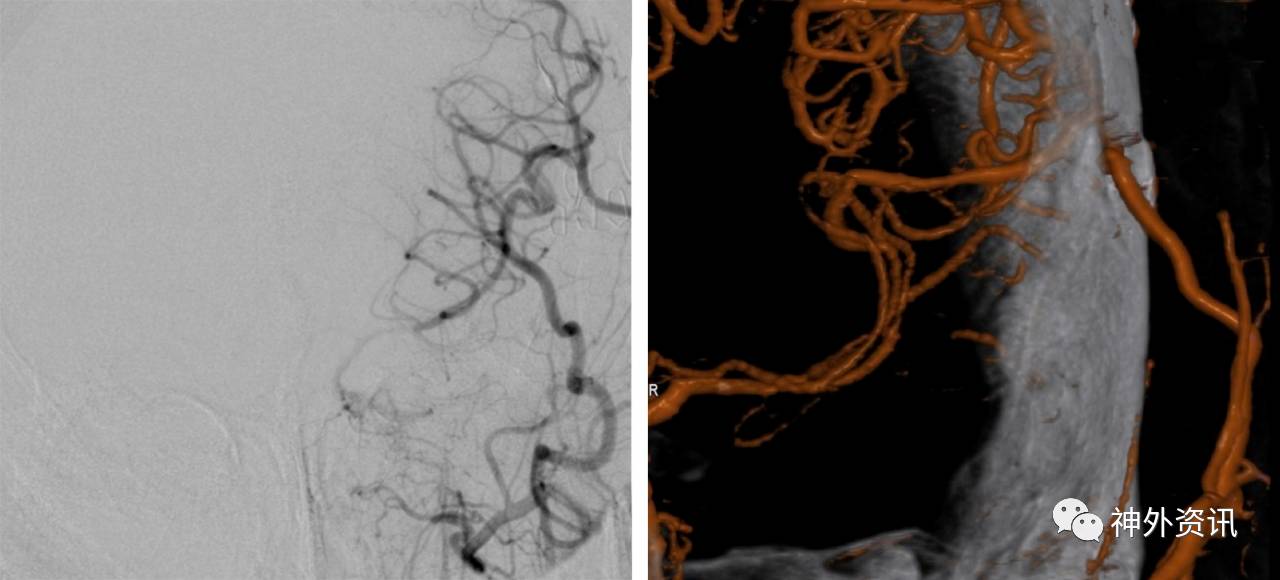

图12. 患者出院后定期随诊复查导管造影或者CTA来评价搭桥的通畅性。此例行左侧STA-MCA搭桥的患者其桥血管保持畅通(右图为三维重建影像)。